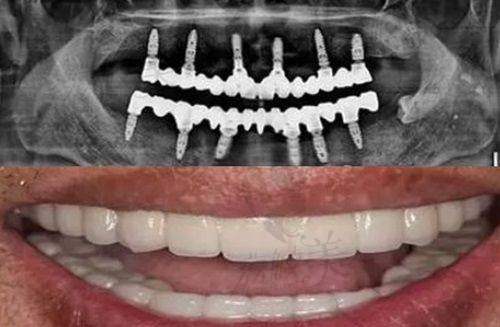

虽然没有明确的资料表明该门诊部具体擅长的项目,但结合口腔门诊部的普遍业务和其招聘信息来看,它可能擅长的项目包括口腔正畸、口腔种植、口腔修复、口腔内科、口腔外科等。从招聘口腔正畸医生的信息可以推测,门诊部在口腔正畸方面可能有一定的实力和需求。口腔正畸可以帮助患者改善牙齿排列不齐、咬合不良等问题,提升口腔美观和功能。而口腔种植则可以为缺失牙患者提供有效的修复方案,修复牙齿的咀嚼功能。口腔修复和口腔内科、外科等项目也是口腔门诊部常见的业务,能够满足患者不同的口腔健康需求。

目前虽然没有直接关于该门诊部仪器设备的详细信息,但考虑到其在当地的排名和口碑,以及口腔医疗行业的发展趋势,推测其可能配备了一些精良的仪器设备。例如,口腔综合治疗台是口腔诊疗中必不可少的设备,它可以为医生提供便捷的操作平台,同时为患者提供舒适的治疗体验。数字化口腔全景机可以拍摄口腔全景片,帮助医生全方面了解患者的口腔状况,为诊断和治疗提供正确的依据。此外,还可能配备了口腔种植机、牙齿美白仪、根管治疗仪等设备,以满足不同口腔项目的治疗需求。